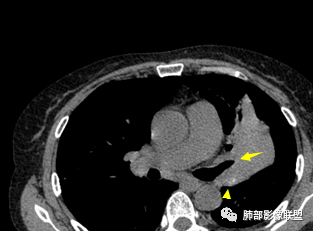

左上胸缩小,但是左上叶部分实变,边缘膨隆,内部有含气支气管,粘液栓,近端支气管堵塞

前端支气管通畅,部分稍扩张,走形自然

实变区支气管内粘液栓明显

上叶支气管堵塞处稍萎缩、凹陷,附近壁增厚,内可见小点状钙化

树芽征、小叶间隔增厚,淋巴结, 内部血管走形自然

分析:支气管粘液栓、支气管堵塞处萎缩、钙化,支气管通畅处部分扩张,树芽征——提示结核。

病灶膨隆明显,支气管堵塞,附近壁增厚,是否需要警惕恶性?